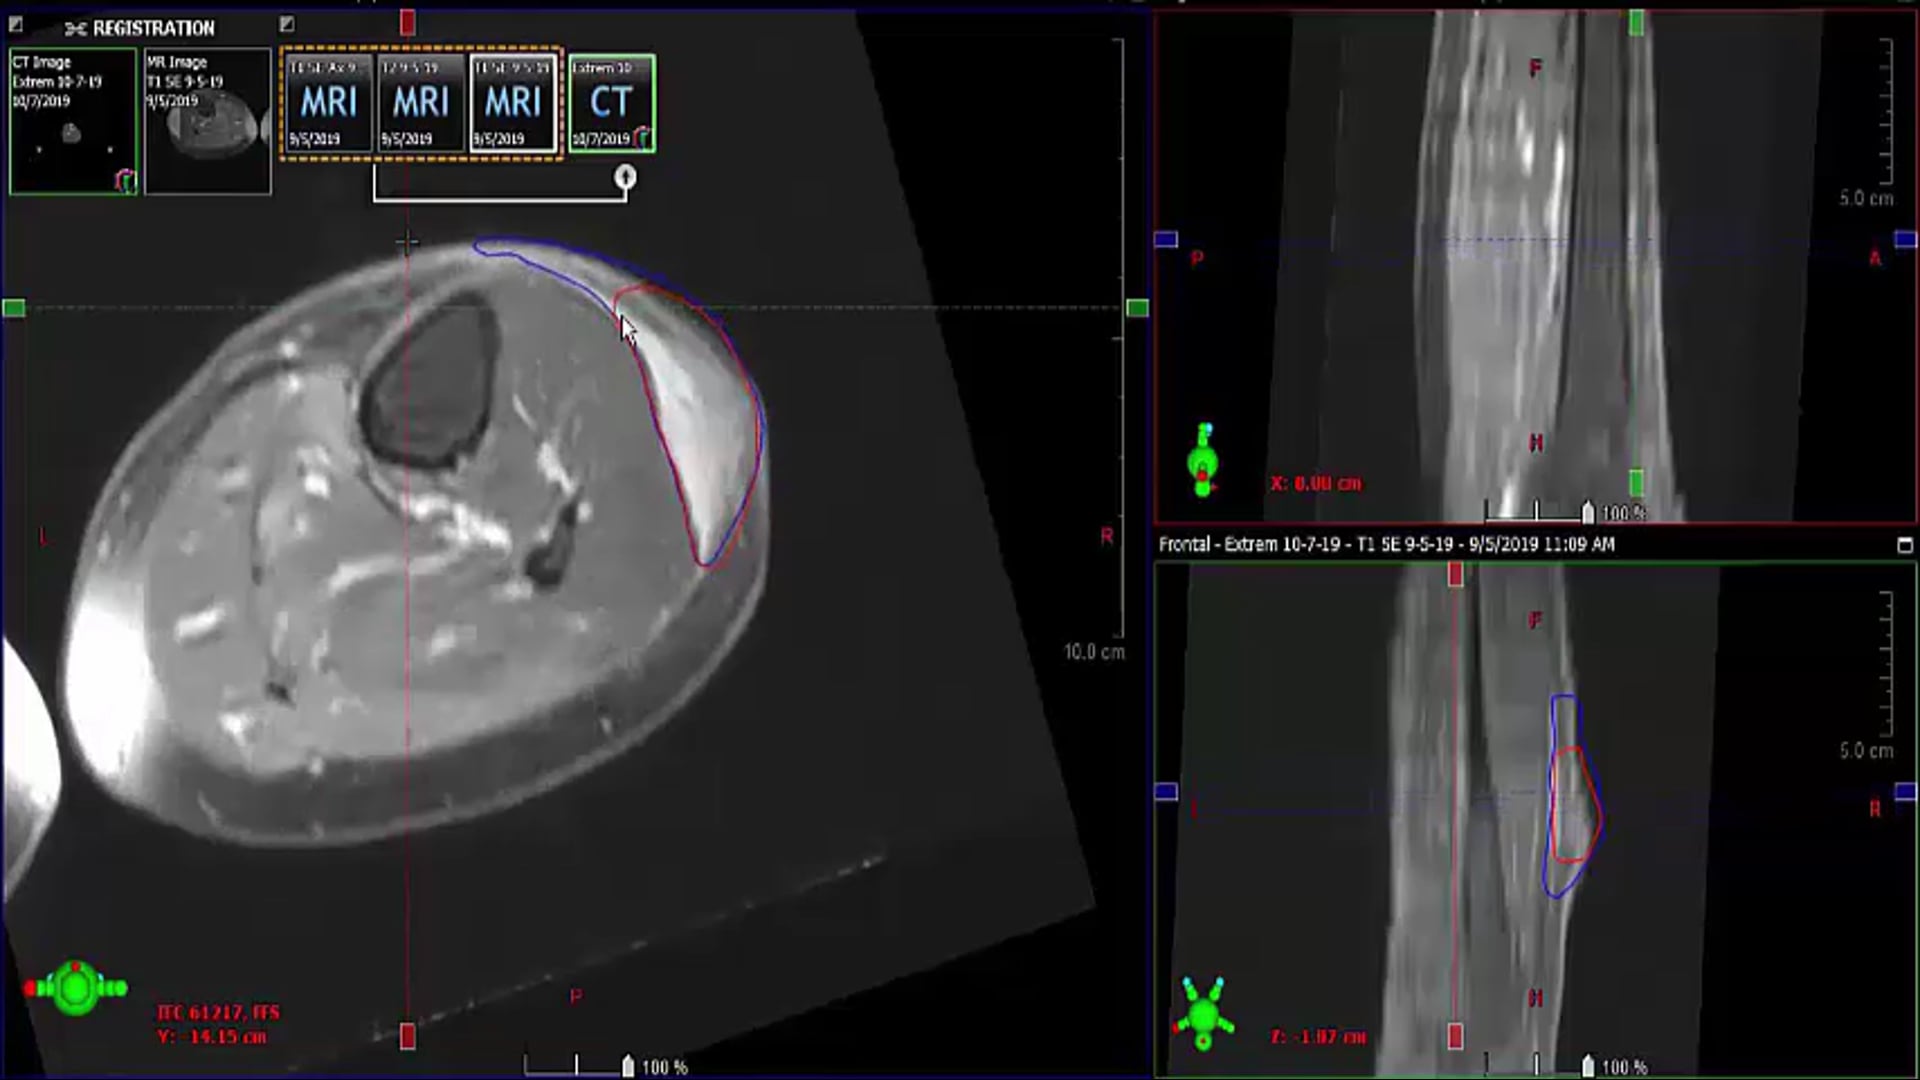

10/10/19 - Dr. Elizabeth Baldini - Radiation Oncology - Sarcoma US